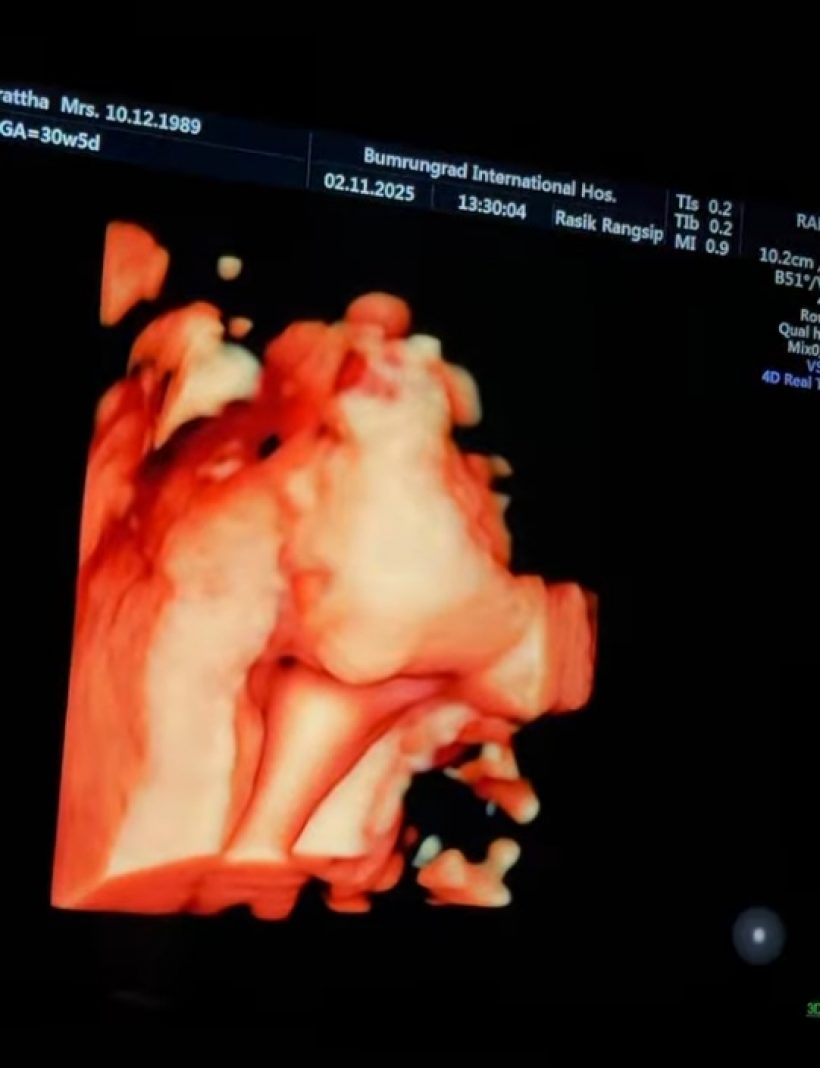

ล่าสุด สาวเนยโพสต์อินสตราแกรม @warutthaim เผยภาพตรวจครรภ์ตามนัด และเผยให้เห็นภาพอัลตร้าซาวด์เบบี๋ เห็นใบหน้าเบบี๋ที่แฟนๆต่างหลงรักตั้งแต่ในท้อง พร้อมแคปชั่นระบุว่า "Everything's just perfect เริ่มกลับหัวแล้ว! ทุกอย่างดีแข็งแรง น้ำหนักดี! คลอดง่ายๆนะลูก!!!!#babykeithonboard"